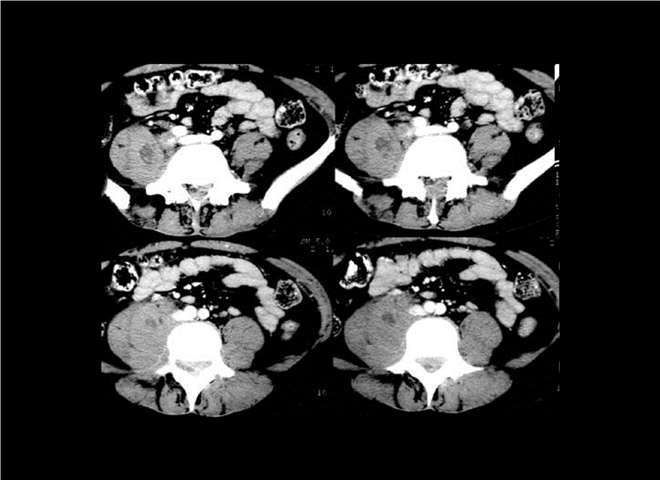

13_CT增强扫描